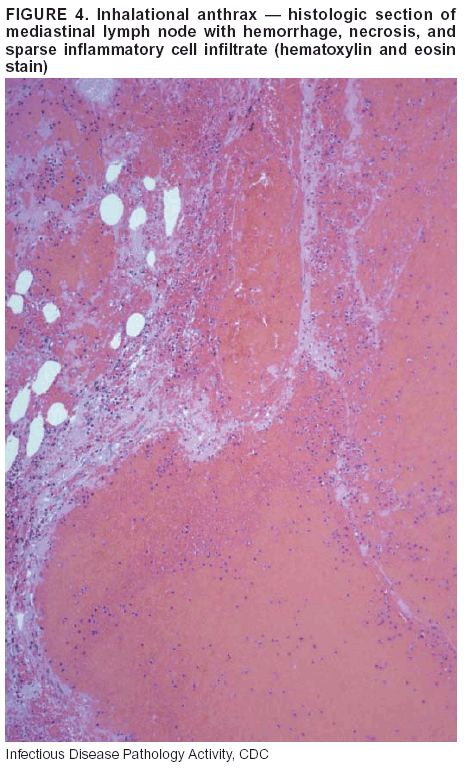

Pathologic Findings. Anthrax has three pathologic forms. Cutaneous anthrax is characterized by an eschar that forms where the bacteria entered the skin (Figure 2). Microscopically, the epidermis has necrosis and crusts, whereas the dermis demonstrates necrosis, edema, hemorrhage, perivascular inflammation, and vasculitis. The lymph nodes that drain the skin site eventually become enlarged, necrotic, and hemorrhagic. Gastrointestinal anthrax is distinguishable by hemorrhagic ulcers in the terminal ileum and caecum accompanied by mesenteric hemorrhagic lymphadenitis and peritonitis. Inhalational anthrax is characterized by hemorrhagic mediastinal lymphadenitis (Figure 3) accompanied by pleural effusions. Histologically, lymph nodes have abundant edema, hemorrhage, and necrosis with limited inflammatory infiltrate (Figure 4) (18,25--29). As any of the three anthrax forms progresses, the bacteria can spread to abdominal organs, producing petechial hemorrhages, and to the central nervous system, producing hemorrhagic meningitis (i.e., cardinal's cap) (Figure 5).